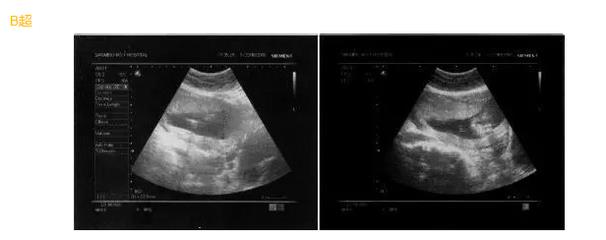

- 01

B超采用的是超声诊断技术,通过一个超声探头发射超声波,使超声波遇到屏障传回声波,我们可以利用电脑收集这些声波,转换成二维图像在屏幕上显示出来。但是B超通过超声探头测得的图像是黑白的,只能观测到胎儿的组织结构,测量胎儿的大概尺寸。